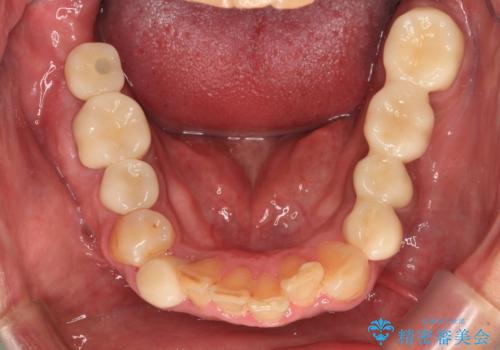

- 黄ばんだ前歯や目立つ奥歯の銀歯をきれいにしたいとのことで来院された患者様です。

欠損している歯や、割れてしまって抜歯の必要な歯などがあり、咬合力が強いため欠損部はインプラント補綴を前提に治療を行うこととしました。

しかしながら、左下の抜歯部位は骨欠損が著しく大きく、多大な垂直的骨造成を要するため、3歯を支台としたブリッジによる補綴治療とし、右下のみをインプラント補綴としました。

小さい修復物の銀歯が装着されている歯はセラミックインレーにて、その他はオールセラミッククラウンにて補綴治療を進めることとしました。